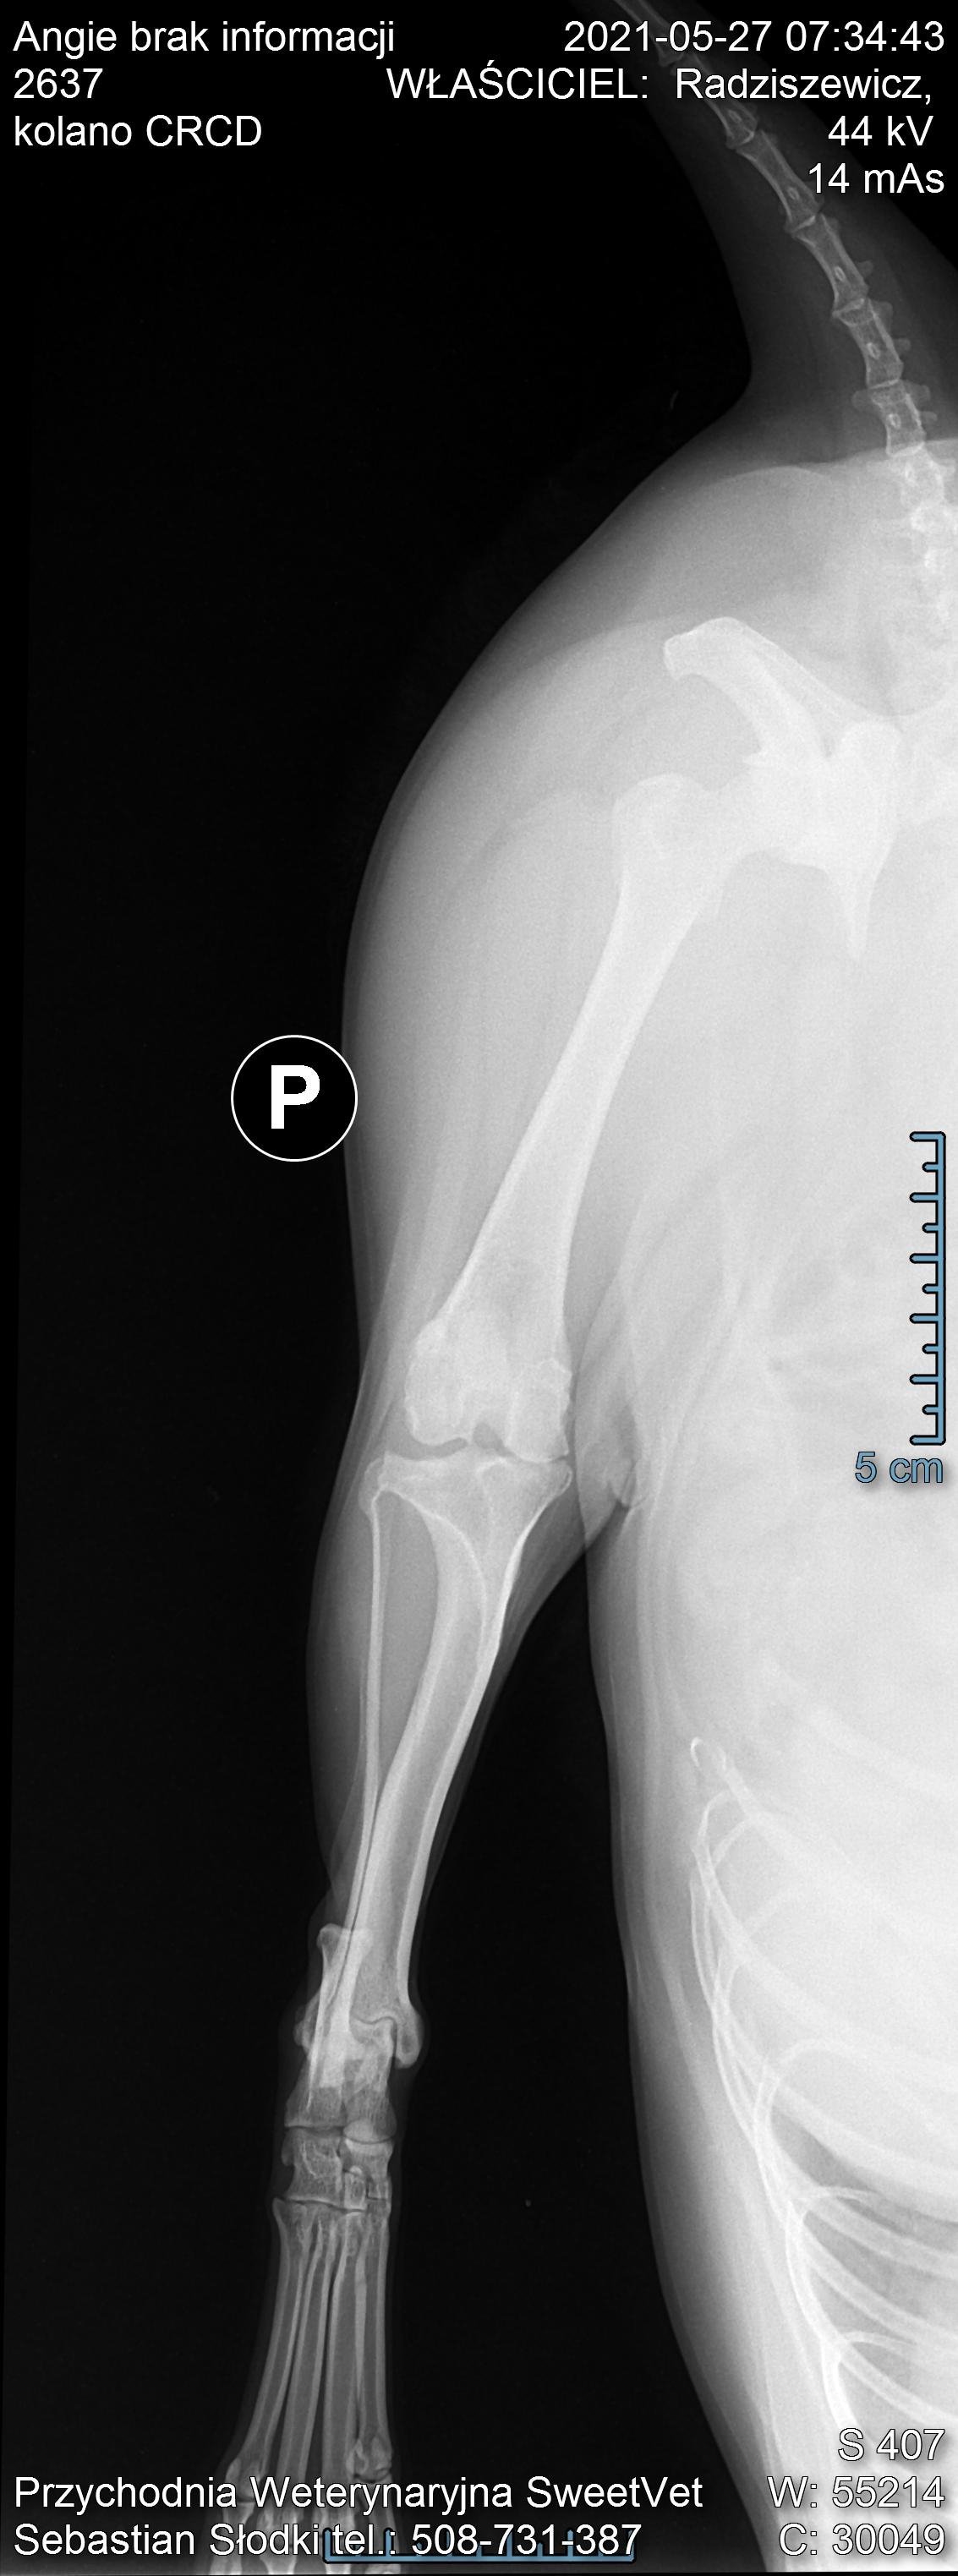

Na nasze szczęście wraz z początkiem maja dostaliśmy możliwość odbywania raz w tygodniu zajęć praktycznych na uczelni w Bydgoszczy. Jako, że mieliśmy opcję przyprowadzić na zajęcia własne zwierzęta i na nich ćwiczyć, zabrałam ze sobą moją Angie. Już na pierwszych zajęciach sunia pokazała dużą bolesność mięśni grzbietu. Tydzień później przy próbach masażu kończyn miednicznych psinka zareagowała agresywnie, od razu dała znać, że nie chce być tam dotykana. Na naszej uczelni przyjmuje fizjoterapeuta zwierząt, więc postanowiłam zaprowadzić tam swojego psa. Okazało się, że mięśnie tylnich łap i kręgosłupa są tak pospinane, że wywołują bardzo dużą bolesność. Przez odciążanie prawej (gorszej) łapki, mięśnie lewej są ciągle spięte, obolałe, przeciążone. Zaczęłyśmy działać przeciwbólowo i rozluźniająco poprzez laseroterapię, ultradźwięki i magnetoterapię. Pani zoofizjoterapeutka poleciła mi jeszcze zrobić dokładne zdjęcia RTG w jednej z bydgoskich klinik (ponieważ bez nich ciężko było wykluczyć bądź potwierdzić wskazania do zabiegu).

Nie zamierzałam się poddać i jeszcze w tym samym tygodniu pojechałam do kliniki Sweetvet na zdjęcia i konsultacje. Okazało się, że mimo tak dużej przestrzeni czasowej od wstępnej diagnozy stawy kolanowe Angie nie są w tragicznym stanie: lewa rzepka-zwichnięcie 2-ego stopnia, prawa- 3-ego. Zdjęcia RTG wykazały zwyrodnienia rzepki i głowy kości udowej w obu kończynach. Bez zabiegu sulkoplastyki i transpozycji guzowatości kości piszczelowej pogłębiające się z czasem zwyrodnienia doprowadzą do zerwania więzadeł. Doktor potwierdził, że Angie jako zdrowy pies, z dobrymi wynikami jak najbardziej nadaje się do operowania, tym bardziej, że teraz jesteśmy w stanie kolosalnie zmienić jej komfort życia.